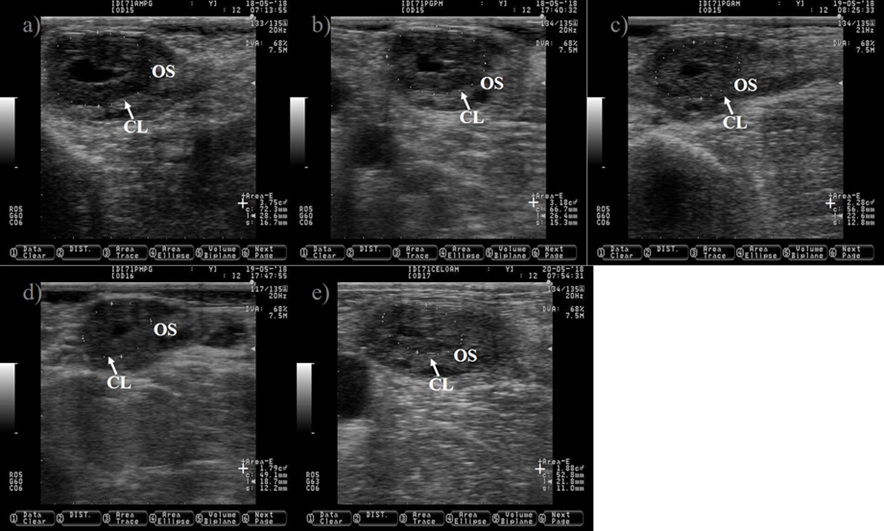

a, c, d and e) CL with luteal cavity (*) of different sizes. b and f) CL without luteal cavity.

OS= ovary stroma; += area of the corpus luteum. Pictures were taken using a 7.5 MHz probe.

Figure 5 Pictures depicting different corpus luteum (CL) shapes at nine days after estrus in Holstein dairy cattle

Pictures were taken at approximately 12 h interval after prostaglandin injection until estrus detection using a 7.5 MHz probe. a) CL just before prostaglandin injection. b) CL 10 h after prostaglandin injection, notice the reduction in its size (+). c) CL showing 39 % reduction in its size 25 h after prostaglandin injection. d) CL showing 52 % reduction in its size 34 h after prostaglandin injection. e) picture depicting the regressed CL 48 h after prostaglandin injection, notice that the CL and the ovary stroma (OS) are almost isoechogenic. The picture was captured a few hours after the cow was detected in estrus, the preovulatory follicle was located in the opposite ovary and it is not shown.

Figure 6 Pictures depicting corpus luteum (CL) regression after prostaglandin injection in Holstein dairy cattle